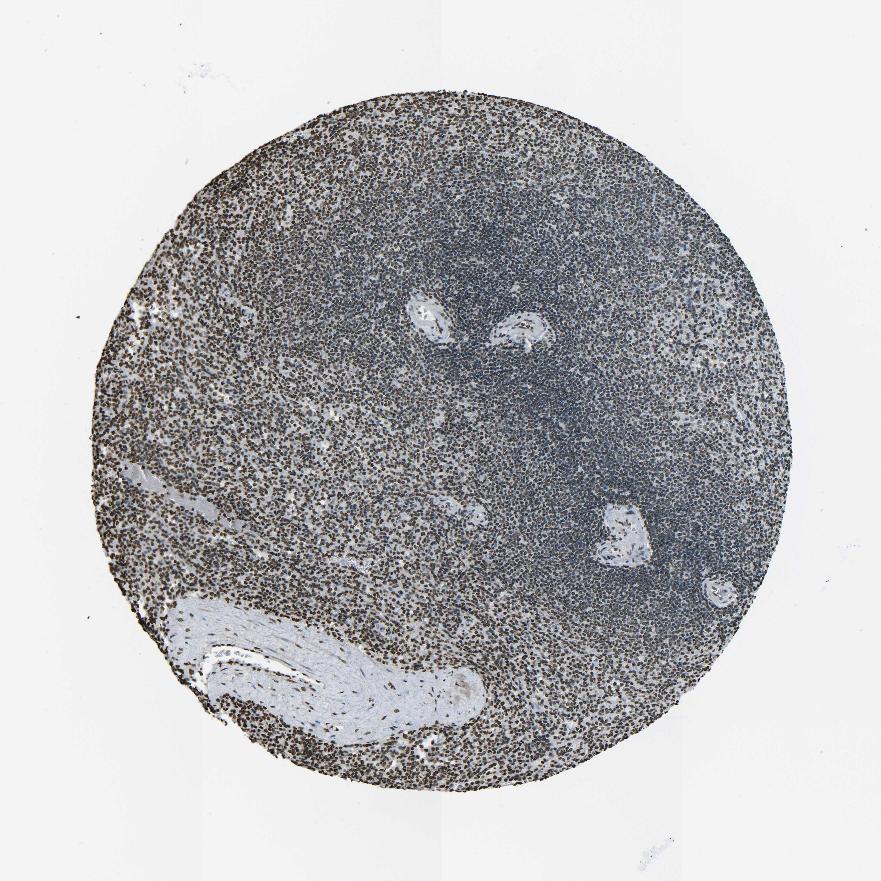

TISSUE PRIMARY DATA SPLEEN Show tissue menu

SPLEEN - Antibody stainingi

Antibody staining in the annotated cell types in the current human tissue is reported as not detected, low, medium, or high, based on conventional immunohistochemistry profiling in selected tissues. This score is based on the combination of the staining intensity and fraction of stained cells.

Each image is clickable and will lead to virtual microscopy that enables deeper exploration of all samples and also displays staining intensity scores, fraction scores and subcellular localization as well as patient and tissue information for each sample.

Antibody HPA042201Antibody CAB011503Antibody CAB037279

Cells in red pulp LowMediumHigh

Cells in white pulp MediumMediumHigh